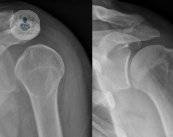

• artroscopia-de-hombro-cirugia

Detalles sobre la artroscopia de hombro

¿Qué resultados ofrece una artroscopia de hombro? ¿Qué patologías se pueden detectar gracias a ella? Este artículo te sacada de dudas. ¡Descúbrelo!